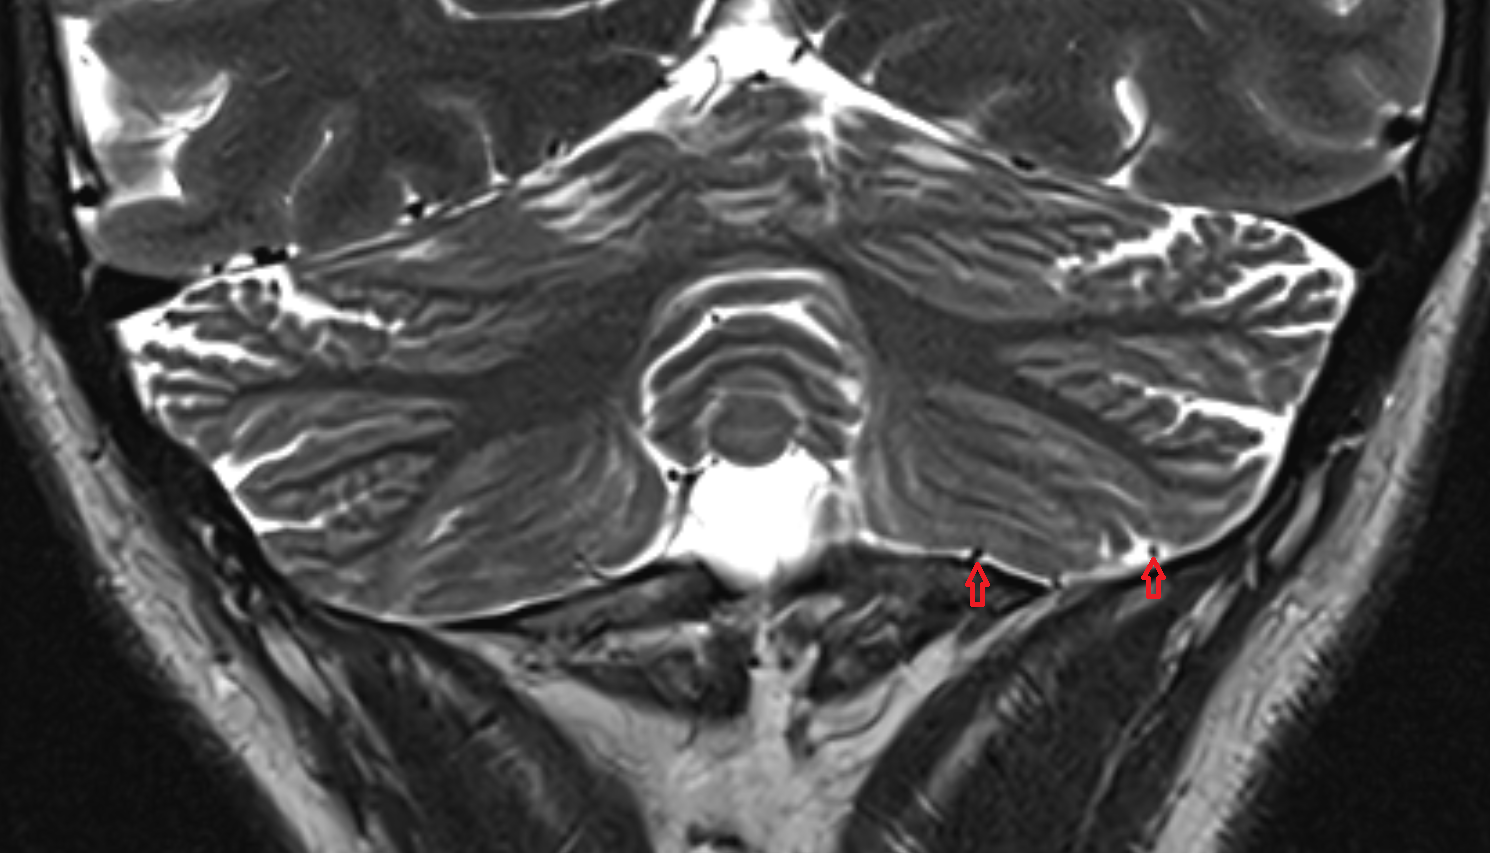

- Cerebellum

- Crus I of ansiform lobule of cerebellum

- Crus II of ansiform lobule of cerebellum

- Paramedian lobule (HVII) of cerebellum

- Simple lobule (HVI) of cerebellum

- Anterior quadrangular lobule (HV) of cerebellum

- Biventral lobule (HVIII) of cerebellum